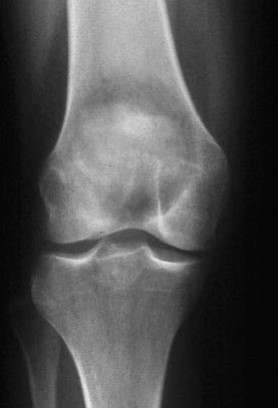

What is this?

Ewing’s Sarcoma